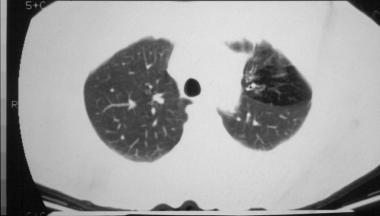

?空气潴留征:在呼气阶段获得的HRCT很容易发现空气潴留征 , 约81%的患者可发现过度充气 。

图6 左上叶的局部过度充气 , 且可见支气管壁增厚

?马赛克症是HRCT扫描中小气道异常的第二个征象 , 约64%的患者可见马赛克症 。

?支气管壁增厚 , 约48%-76%的患者可见支气管壁增厚 。

?支气管扩张:支气管扩张是最常见的CT异常 , 约80%的患者可见支气管扩张 , 可见柱状型、曲张型和囊状型扩张 。